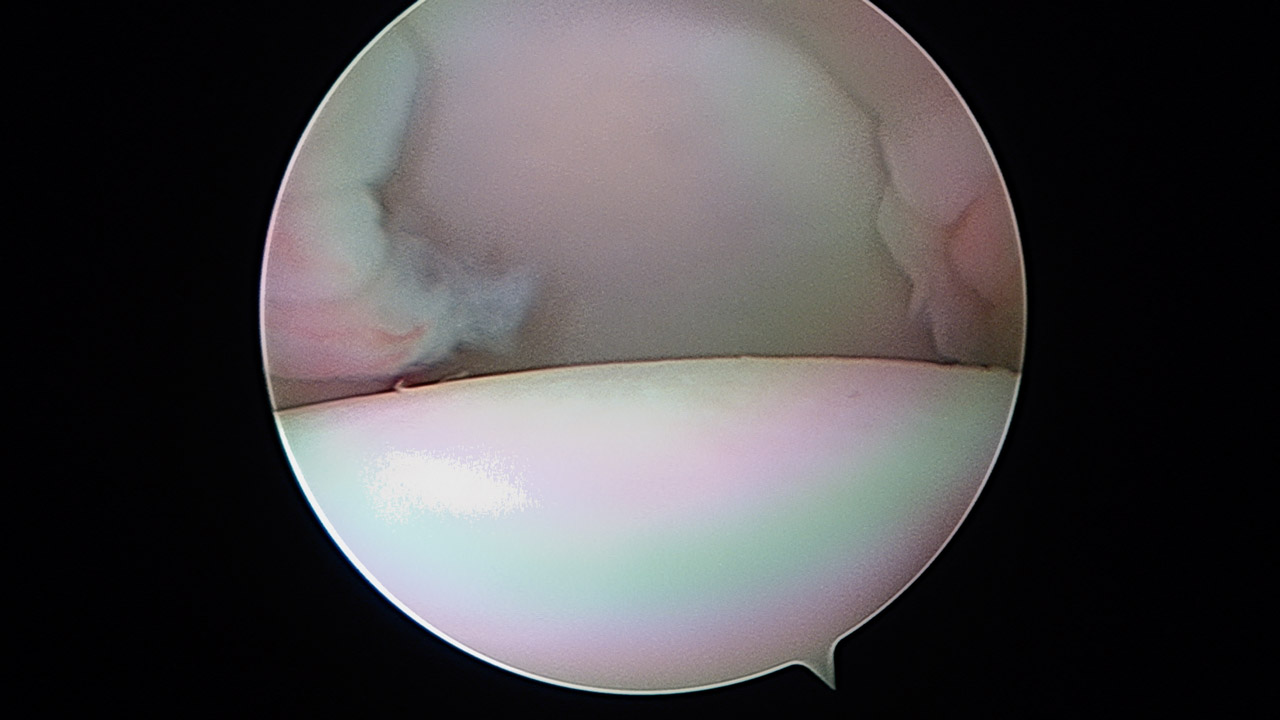

Las ventajas de dicha técnica son la disposición transubescapular como ya describiera Cuéllar(12), permitiendo la estabilidad del hombro en posición de lanzamiento, ya que no se descubre la cabeza humeral en abducción y rotación externa por ascenso del subescapular. Otra ventaja es la realización artroscópica de la técnica (Figura 1) (vídeo disponible en la versión online de la REACA).